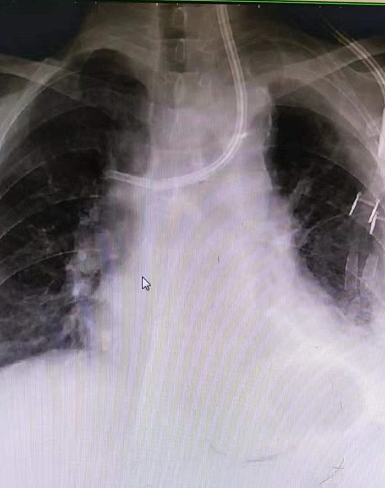

王女士,确诊尿毒症7+年时间,长期依靠左侧cuff导管行血液透析治疗,因确诊导管感染,经过反复治疗后效果不佳,所以必须拔除维持患者生命的唯一的血管通路,但是血管通路是尿毒症患者维持生存的必备条件,目前患者又处于病危状态、高钾、水负荷重,心衰明显,必须立即建立新的血管通路行血液透析治疗去维持生命,由于患者自身血管条件差,动静脉内瘘建立困难,临时血管通路建立难度极大,临时安置股静脉导管、颈内静脉导管均失败,不能满足血液透析要求,对此,患者悲痛欲绝、陷入绝望,家属也不放弃任何能够救治的机会,啃啃哀求郑医生能够为患者开辟一条“活路”;于是肾病科主任毕伟红、副主任王婷立刻紧急召开血管通路小组会议,由于王女士基础疾病多且复杂,DSA下造影显示左侧头臂静脉重度狭窄伴血栓形成,手术难度及风险极大,经过讨论,主刀医生郑星和张艳玲医生快速为患者量身定制手术方案,决定联合运用介入技术(DSA)+PTA技术,为王女士开辟一条新的“活路”。王女士,确诊尿毒症7+年时间,长期依靠左侧cuff导管行血液透析治疗,因确诊导管感染,经过反复治疗后效果不佳,所以必须拔除维持患者生命的唯一的血管通路,但是血管通路是尿毒症患者维持生存的必备条件,目前患者又处于病危状态、高钾、水负荷重,心衰明显,必须立即建立新的血管通路行血液透析治疗去维持生命,由于患者自身血管条件差,动静脉内瘘建立困难,临时血管通路建立难度极大,临时安置股静脉导管、颈内静脉导管均失败,不能满足血液透析要求,对此,患者悲痛欲绝、陷入绝望,家属也不放弃任何能够救治的机会,啃啃哀求郑医生能够为患者开辟一条“活路”;于是肾病科主任毕伟红、副主任王婷立刻紧急召开血管通路小组会议,由于王女士基础疾病多且复杂,DSA下造影显示左侧头臂静脉重度狭窄伴血栓形成,手术难度及风险极大,经过讨论,主刀医生郑星和张艳玲医生快速为患者量身定制手术方案,决定联合运用介入技术(DSA)+PTA技术,为王女士开辟一条新的“活路”。王女士,确诊尿毒症7+年时间,长期依靠左侧cuff导管行血液透析治疗,因确诊导管感染,经过反复治疗后效果不佳,所以必须拔除维持患者生命的唯一的血管通路,但是血管通路是尿毒症患者维持生存的必备条件,目前患者又处于病危状态、高钾、水负荷重,心衰明显,必须立即建立新的血管通路行血液透析治疗去维持生命,由于患者自身血管条件差,动静脉内瘘建立困难,临时血管通路建立难度极大,临时安置股静脉导管、颈内静脉导管均失败,不能满足血液透析要求,对此,患者悲痛欲绝、陷入绝望,家属也不放弃任何能够救治的机会,啃啃哀求郑医生能够为患者开辟一条“活路”;于是肾病科主任毕伟红、副主任王婷立刻紧急召开血管通路小组会议,由于王女士基础疾病多且复杂,DSA下造影显示左侧头臂静脉重度狭窄伴血栓形成,手术难度及风险极大,经过讨论,主刀医生郑星和张艳玲医生快速为患者量身定制手术方案,决定联合运用介入技术(DSA)+PTA技术,为王女士开辟一条新的“活路”。郑星医生表示在:介入技术能够快速发现患者血管通路问题所在,能让“隐形”的血管可视化,精准定位,提高手术操作成功率;由于王女士左侧头臂静脉重度狭窄伴血栓形成,导管通过狭窄部位困难,然而利用PTA技术能够扩张血管重度狭窄部位,让导管顺利通过,两种技术联合运用,极大地降低手术风险,减少了患者的痛苦。生命线的顺利重置,血液透析治疗的顺利开展,让患者及家属顿时喜笑颜开,重燃了患者生存的希望。

(术前) (术前) (术后)

介入技术(DSA):指通过在血管中注入造影剂,使血管显影,根据血管的分布、形态、位置等变化来判断病变的具体部位、范围及程度,并可经导管行介入治疗。

经皮血管腔内血管成形术(PTA):通过经皮穿刺血管,置入导丝,沿导丝将球囊输送至血管狭窄病变处,将扩张球囊送入血管狭窄部位并对其进行扩张,从而将狭窄血管矫正至正常血管内径。